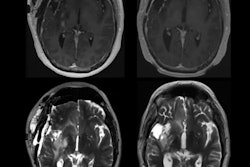

Structural MR imaging, such as T1-weighted exams, are commonly used in memory clinics for diagnosing Alzheimer's disease and differentiating Alzheimer's from other types of dementias, the group explained. Radiologists visually interpret these exams, but these interpretations are subjective and "prone to intrarater and interrater variability," it noted. Using quantitative imaging markers culled from brain volumetric data shows promise for improving readers' diagnostic confidence, and there are AI algorithms that track these. But differences in MRI acquisition protocols and scanners can affect the consistency of brain volumetry assessment.

To this end, Archetti and colleagues developed an extended version of Neuroharmony to track interactions between Alzheimer's disease pathology and image quality metrics in 20,864 individuals with and without cognitive impairment. These data spanned 11 prospective and retrospective study cohorts and 43 scanners. The group then evaluated the expanded algorithm's ability to remove scanner-related variations in brain volumes (that is, to track marker concordance between scanners) while continuing to delineate disease-related signals.